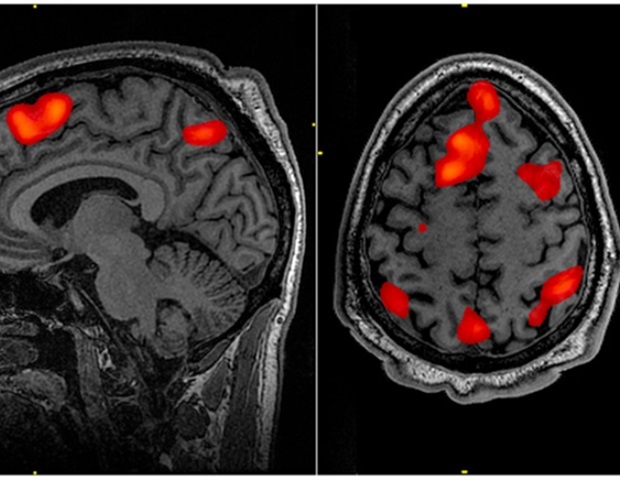

В этом исследовании использовалась нейровизуализация с серо-белым контрастом (GWC), метод на основе МРТ, призванный улучшить исследования здоровья нейронов у травмированных людей. GWC действует как показатель внутрикортикальной плотности миелинизации, исследуя кажущуюся размытость границы раздела белого и серого вещества на основе различий в интенсивности сигнала. Увеличение контрастности представляет собой более резкую границу, указывающую на здоровый переход от серого вещества к белому веществу головного мозга. Менее четкая граница (низкая GWC) предполагает аномальную концентрацию миелина (жирового изолирующего слоя), что указывает на нарушение скорости и последовательности обработки данных в мозге.

Оценивая структурные изображения мозга 99 участников, ответивших на WTC, исследователи обнаружили доказательства широко распространенных изменений в GWC в Снижение GWC в обоих полушариях головного мозга у людей с посттравматическим стрессовым расстройством может означать, что в этих областях содержится больше миелина, чем обычно у людей, подвергшихся травме без посттравматического стрессового расстройства. Они также обнаружили, что GWC можно комбинировать с другими маркерами внутрикоркового здоровья, чтобы улучшить способность объективно идентифицировать людей, реагирующих на WTC, с посттравматическим стрессовым расстройством.

Новое исследование среди участников Всемирного торгового центра (ВТЦ) с хроническим посттравматическим стрессовым расстройством (ПТСР) выявило измеримые физические изменения в структуре их мозга, соответствующие изменениям в балансе миелинизированных и немиелинизированных нейронов (быстро- и медленнопроводящих нервных клеток) в обоих полушариях мозга. Эти изменения были наиболее сильно связаны с повторным возникновением симптомов у людей с посттравматическим стрессовым расстройством. Кортикальные различия, обнаруженные в этом сложном исследовании визуализации в книге Биологическая психиатрия: когнитивная нейронаука и нейровизуализация, опубликованном Elsevier, могут служить суррогатными биомаркерами нарушения здоровья мозга у людей, страдающих хроническим посттравматическим стрессовым расстройством, а также потенциально определять стратегии раннего скрининга.